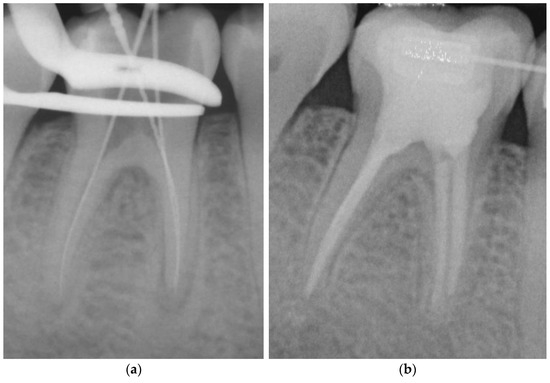

- Adhesive obturation using the continuous wave of condensation technique with Resilon® (CWR) (Figure 1).

Figure 1. Representative example of root canal filling with Resilon® using the continuous wave of condensation technique (CWR); working length radiograph of tooth 36 (a); 6-year follow-up radiograph showing complete apical healing (b). - Matching-taper single-cone obturation with gutta-percha and the epoxy-resin-based sealer AH Plus® (SCGP) (Figure 2).